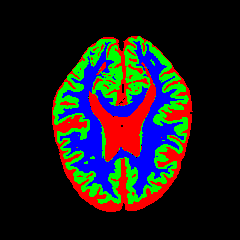

• OASIS-1 [34]: Derived from the Open Access Series of Imaging Studies, this dataset comprises T1-weighted MRI scans from 421 subjects (aged 18–96). The images were acquired with a resolution of 176×208176\times 208 pixels and a slice thickness of 1.25 mm (TR=9.79.7 ms, TE=4.04.0 ms, TI=2020 ms). Following standard protocols, we utilize the provided manual segmentation masks for Cerebrospinal Fluid (CSF), Grey Matter (GM), and White Matter (WM).

7 Qualitative Evaluation

Fig. 8 and Fig. 10 provide qualitative comparisons on the OASIS-1 and MRBrainS13 datasets, respectively. It is visually evident that the baseline predictions (c) and standard augmentations (e.g., (d), (g), (i)) frequently suffer from noisy artifacts, blurred boundaries, and mis-segmentation of intricate anatomical structures. In stark contrast, our ”Ours+” enhanced methods (e.g., (e), (h), (k)) consistently produce segmentation maps that are visibly cleaner, more spatially coherent, and demonstrate significantly sharper adherence to the Ground Truth (b). This superior fidelity is particularly noticeable in the complex sulcal patterns and holds true across all three backbones (rows), confirming that our framework yields more robust and anatomically plausible results.